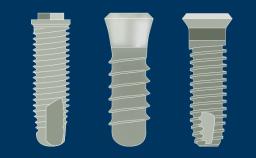

Introduction to Implant Dentistry

Implant Designs and Characteristics

Learning Module